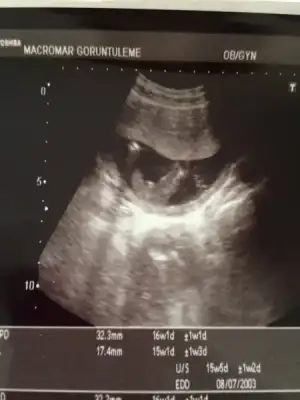

Selam hanımlar, bende dün sırf cinsiyetini öğrenip eşime süpriz yapayım akşam diye bu soğukta doktora gittim, ikili taramada 12 haftalık falandı o zmn kıza benzetti, ama emin değildi , dünde erkeğe benzetti ama yine emin değil Ultrason görüntüsünde erkek gibi geldi , sizden de yorum alabilir miyiz acaba☺️

Bacaklarimi o galiba acmis kiz sanki canim bi kabariklik yok cunku

Eklentiler

• IMG_2334.webp